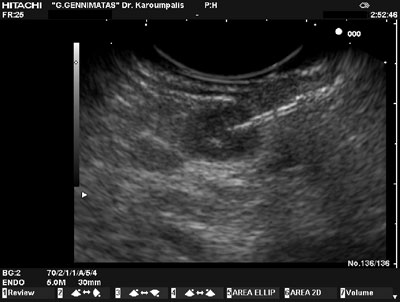

Following the biochemical confirmation of hyperinsulinemia an attempt to localize the insulin secreting-tumour was made. Contrast-augmented CT and MR imaging of the pancreas as well as radionuclear imaging with 111In-octreotide failed to localize a pancreatic lesion. An endoscopic ultrasound identified a tumour at the tail of the pancreas, in close proximity to the spleen. A fine needle aspiration (FNA) was performed in order to acquire enough material for cytological analysis using Medi-Glob 22G needles. Cytology followed by immunocytohemistry for chromogranin and insulin suggested a pancreatic insulinoma. The patient remained normoglycemic while receiving treatment with oral diazoxide (150 mg/day). Subsequently, she underwent a laparotomy and the pancreas was exposed. The tumour was not identified and the tail of the pancreas was mobilized without success. IOUS did not locate the tumour. A soft-tissue mass in close contact with the pancreas was removed. We then elected to close the abdomen in order to avoid unnecessary blind distal pancreatectomy and perform a new EUS later. The patient had an uneventful recovery and two weeks later a further EUS was performed. The examination was carried out using Pentax's EUS EG 3630U and Hitachi's console EUB 6000 Victor, which clearly identified a hypoechogenic lesion of 0.98x0.82cm in size, with clear smooth borders, located in-between the body and tail of pancreas, that showed intense and diffuse vascularization in the Doppler signal. Trans-gastric injection of 1cc methylene-blue in the tumour through fine needle was done for tattoing the lesion (Figure 1).

Figure 1. Endoscopic ultrasound revealed the small insulinoma.